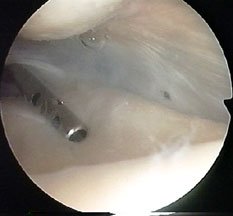

Here are a couple of stills from the video, which just showed a swirling mass of undefinable tissue -